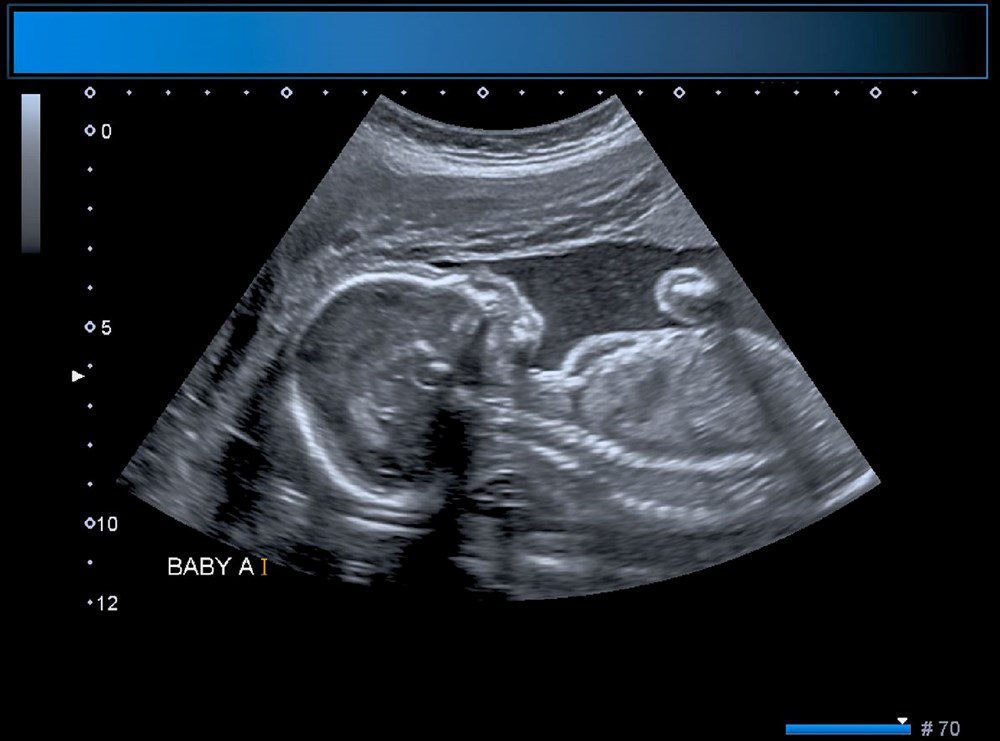

Yeni bir araştırmaya göre, Çin’de doktorlar bir yaşındaki bir çocuğun beyninde ‘doğmamış ikizinin fetüsünü’ buldu. Neurology dergisinde yayınlanan çalışmada, çocuğun motor fonksiyonlarında sorunlar yaşaması ve kafasının büyümesi üzerine ebeveynleri tarafından hastaneye getirildiği ortaya çıktı. Şangay’daki doktorlar, doğmamış ikizin fetüsünün çocuğun beyninde geliştiğini tespit etti. Çalışmanın yazarları, “Motor becerilerinde gecikmesi ve genişlemiş baş çevresi olan 1 yaşındaki bir kız çocuğunda malforme olmuş monokoryonik diamniyotik ikiz olan intraventriküler fetüs içinde fetüs (fetus-in-fetu) tespit edildi.” denildi.

Parazit ikiz olarak da adlandırılan fetüs içinde fetüs, ikizlerin rahimde yapışık olması, ancak yalnızca birinin gelişmeye devam etmesi durumunda ortaya çıkıyor. Çalışmada, genom dizilimi sonrasında fetüsün çocuğun ikizi olduğunun tespit edildiği de belirtildi.